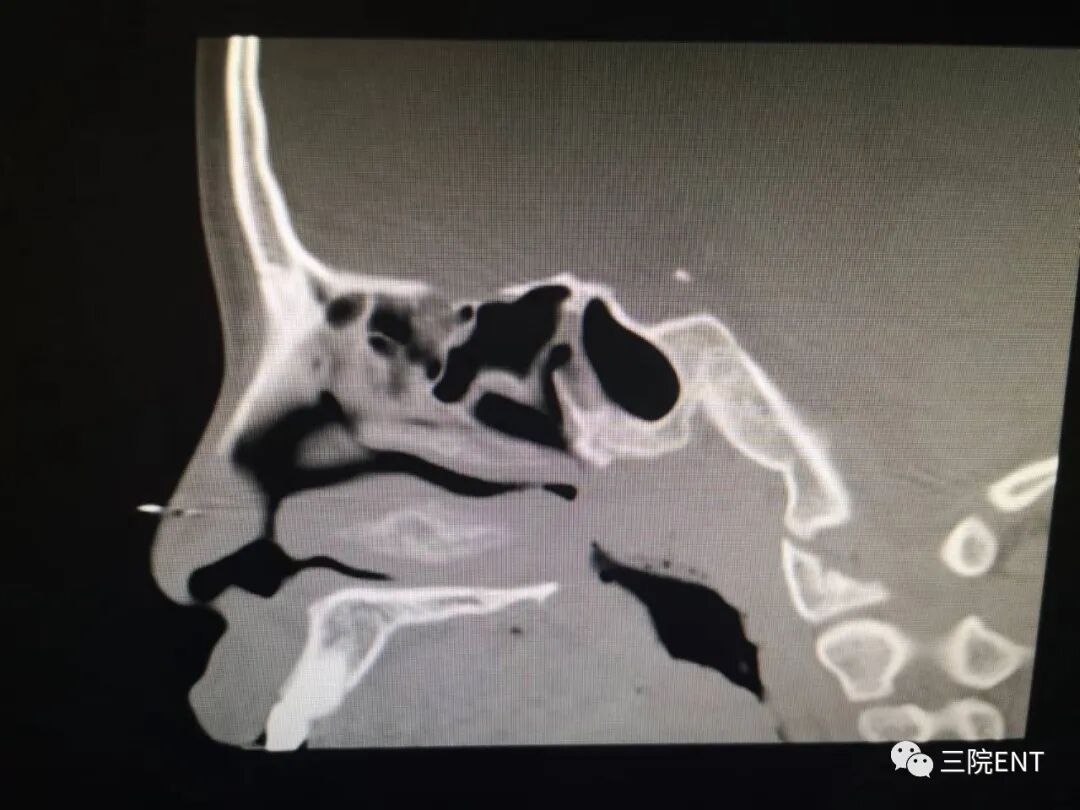

4.鼻内镜检查鼻咽顶后壁可见粉红色软组织团块;鼻咽X线侧位拍片或CT扫描为决定性诊断

图片图片